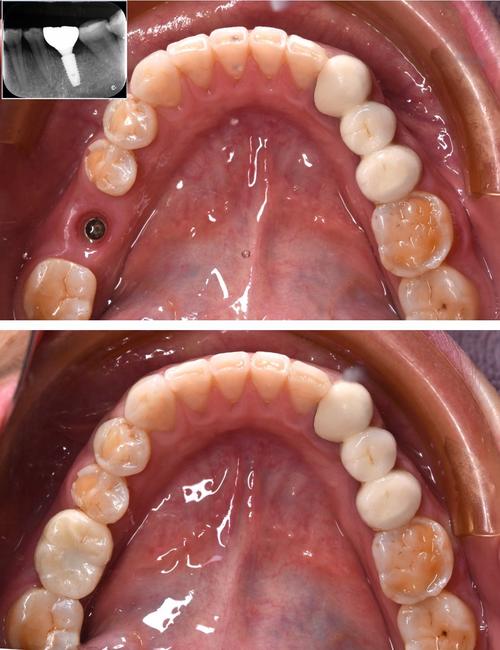

手术植入是种植牙的关键步骤,在局部麻醉下,医生切开牙龈,暴露牙槽骨,使用专用种植机将种植体植入预定位置,随后缝合牙龈,手术时间通常为30分钟-2小时(根据种植数量而定),过程中患者无明显疼痛,术后需服用抗生素预防感染,7-10天拆线,期间避免食用过硬、过热食物。

戴牙冠阶段通常在种植体植入后3-6个月,此时牙槽骨与种植体已完成骨结合,医生会取模,制作个性化的全瓷牙冠或烤瓷牙冠,并通过基台与种植体连接,完成最终的牙齿修复,牙冠的颜色、形态会与邻牙保持一致,达到以假乱真的效果。